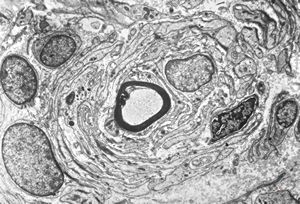

M,10y. | herpetic encephalitis